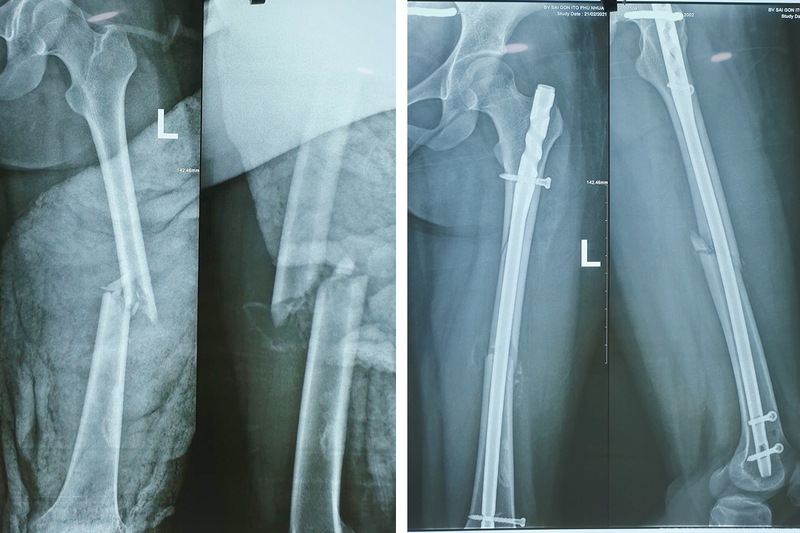

Có một số vấn đề thường gặp ở xương đùi, trong đó gãy cổ xương đùi là một trong những vấn đề phổ biến nhất. Điều này thường xảy ra ở người lớn tuổi và người suy giảm mật độ xương. Ở người trẻ, gãy cổ xương đùi thường xảy ra sau tai nạn hoặc va chạm với lực tác động cao.

Có một số bệnh lý thường gặp ở xương đùi, bao gồm:

Để chẩn đoán và điều trị các vấn đề này, cần phải tham khảo ý kiến của bác sĩ chuyên khoa phù hợp.